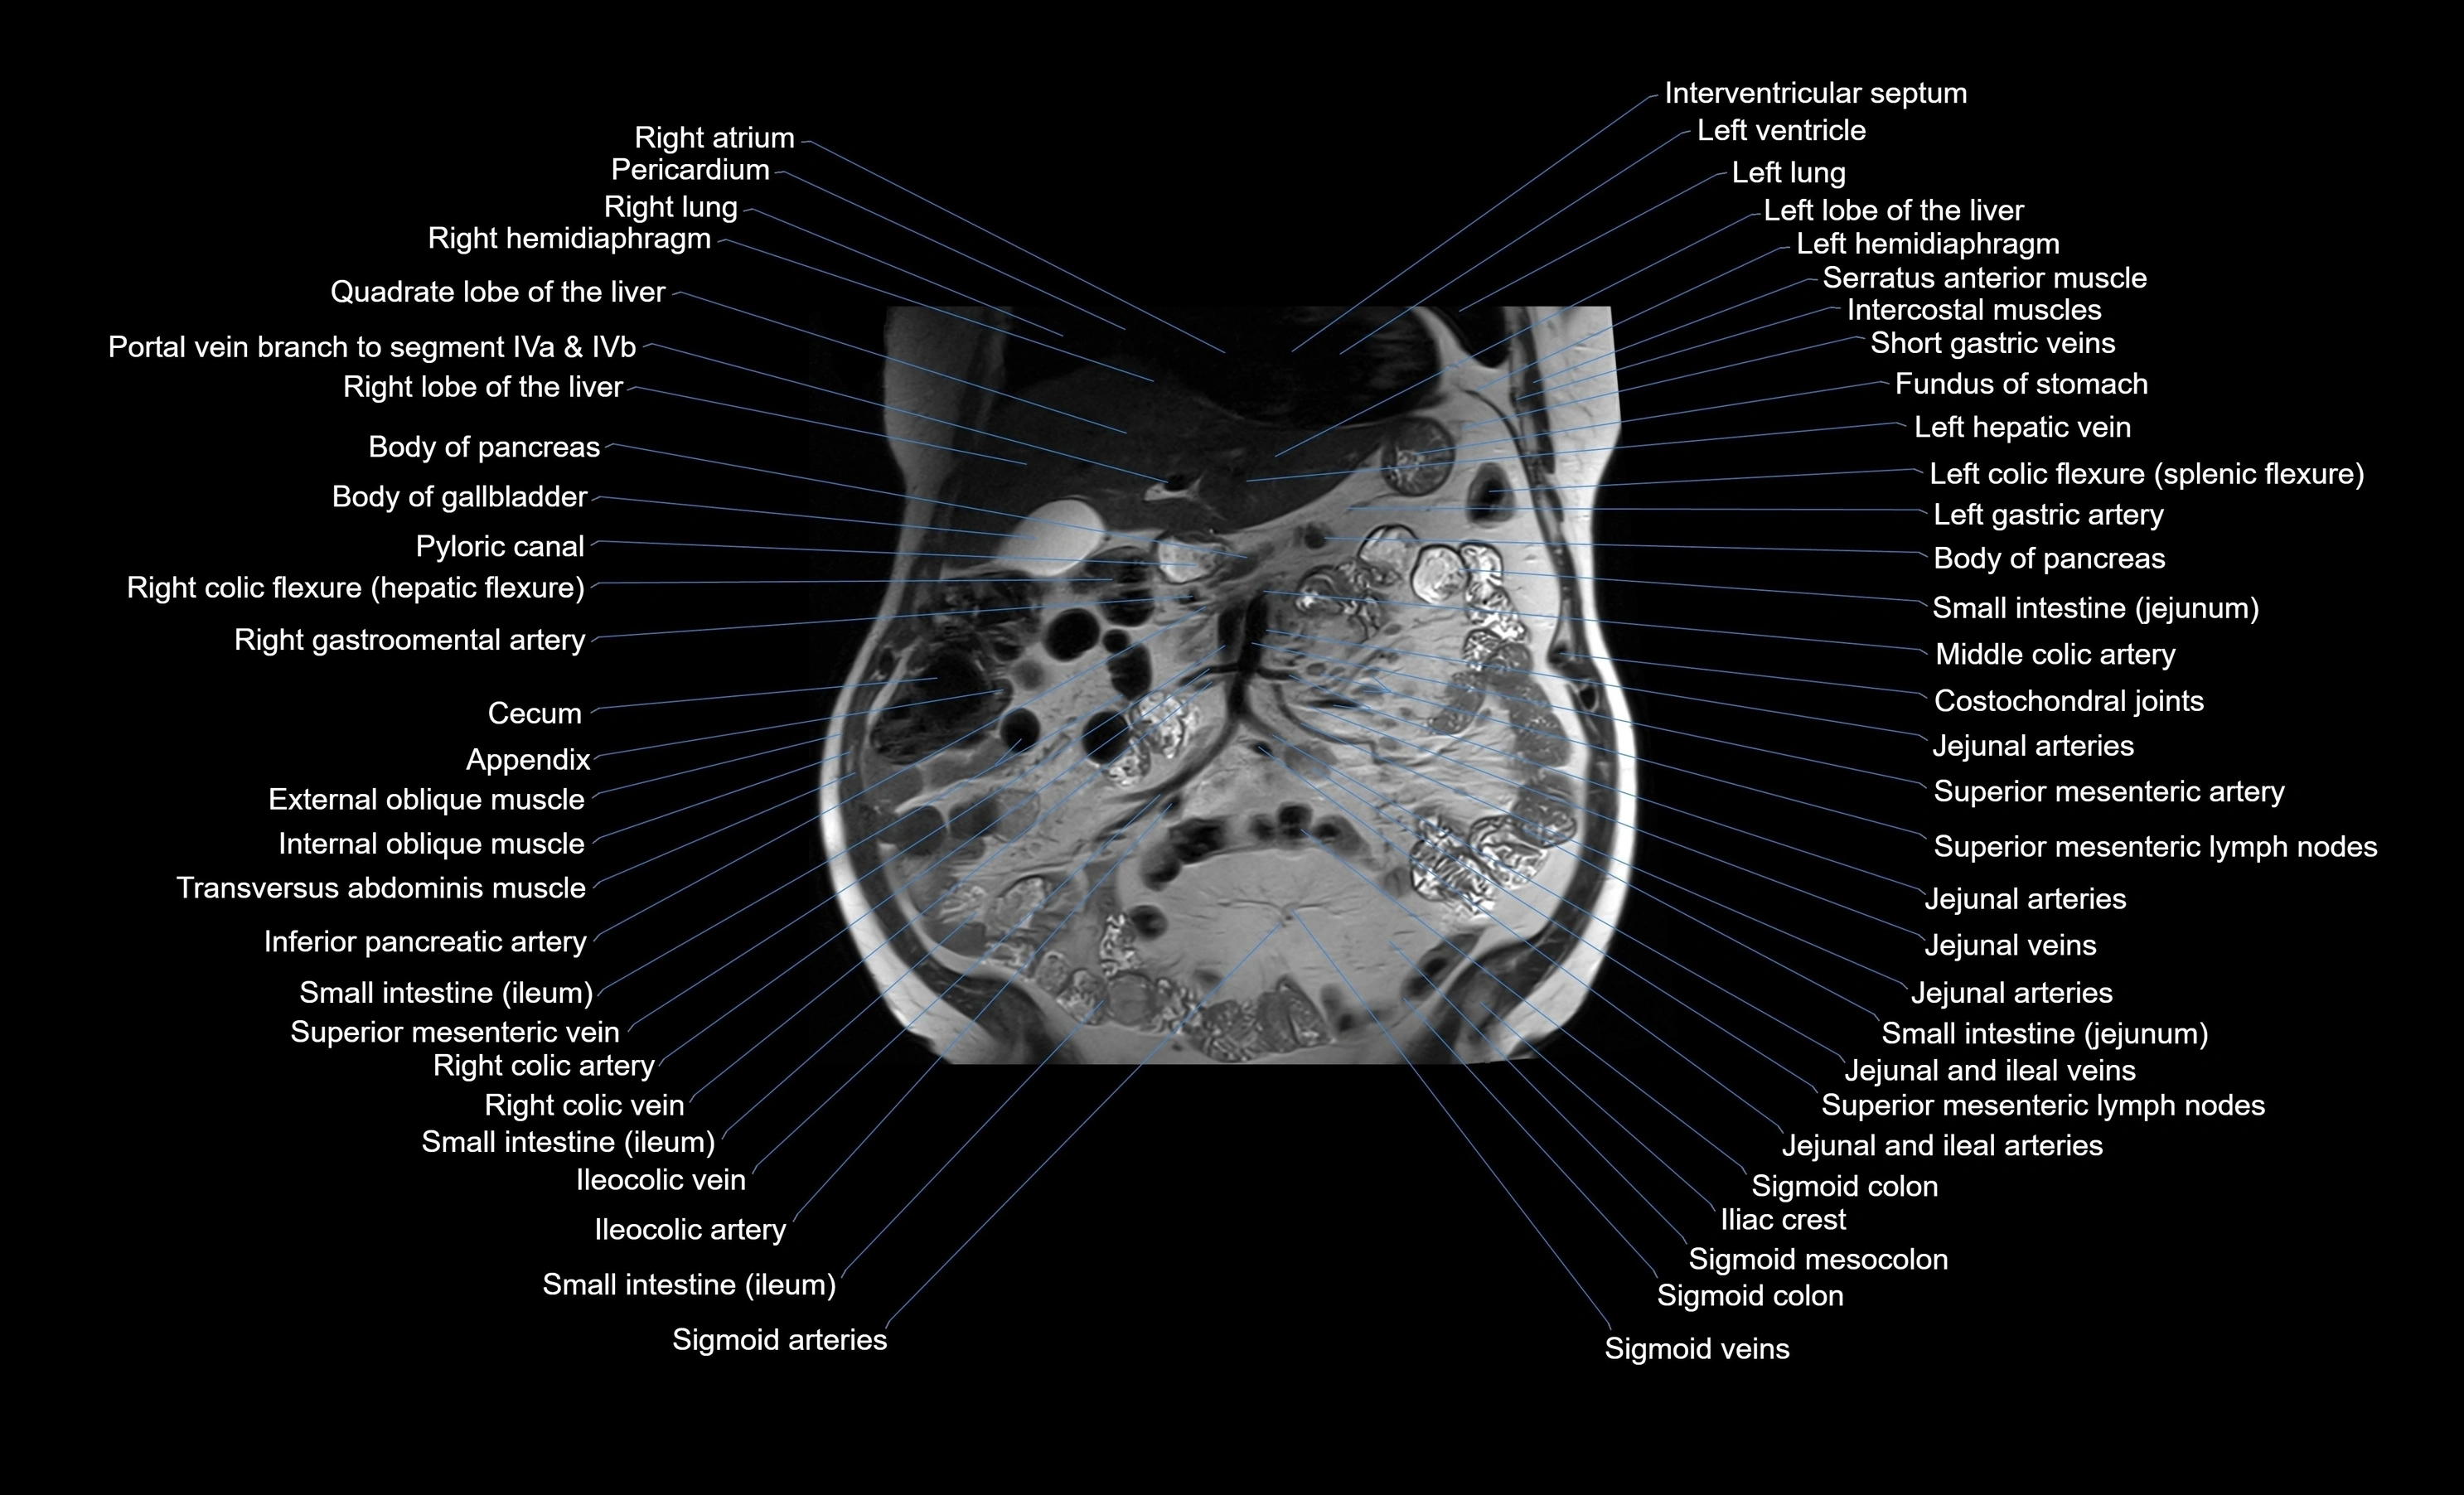

MRI images